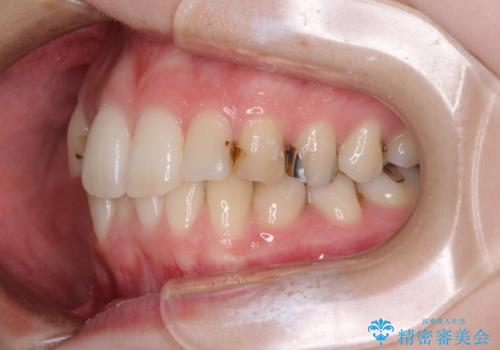

- 前歯のデコボコをクロスバイトを気にして来院された患者様です。

上顎骨の横幅が狭く、上下ともに内側に倒れ込んだ混み合った歯列となっていました。

急速拡大装置により上顎骨を側方に拡大し、ワイヤー装置により歯列を整えることとしました。

矯正治療後には、目立つ銀歯と隣接するむし歯をセラミックインレーにて修復治療することとしました。